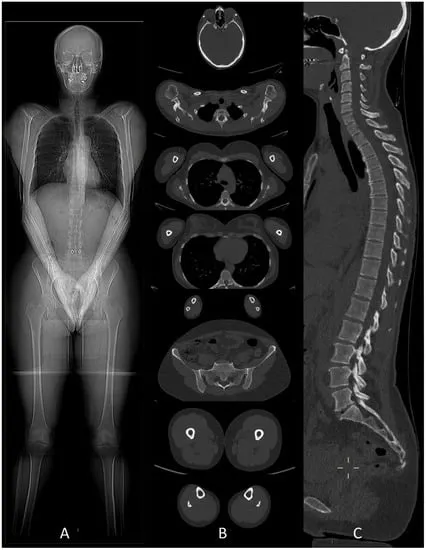

- Whole-Body CT (WBCT) / Pan-Scan: Rapid, comprehensive CT for major trauma.

- Protocol Components:

- NCCT Head & C-spine

- CECT Chest (arterial phase)

- CECT Abdomen & Pelvis (portal venous phase; consider arterial for active bleed, delayed for urothelial injury)

- Advantages: Rapid assessment, ↓ time to diagnosis, potential improved survival in select polytrauma.

- Disadvantages: Radiation (effective dose ~10-25 mSv), contrast risks (CIN, allergic reaction), potential over-investigation.

⭐ WBCT is associated with a survival benefit in patients with severe trauma (Injury Severity Score ISS > 15).